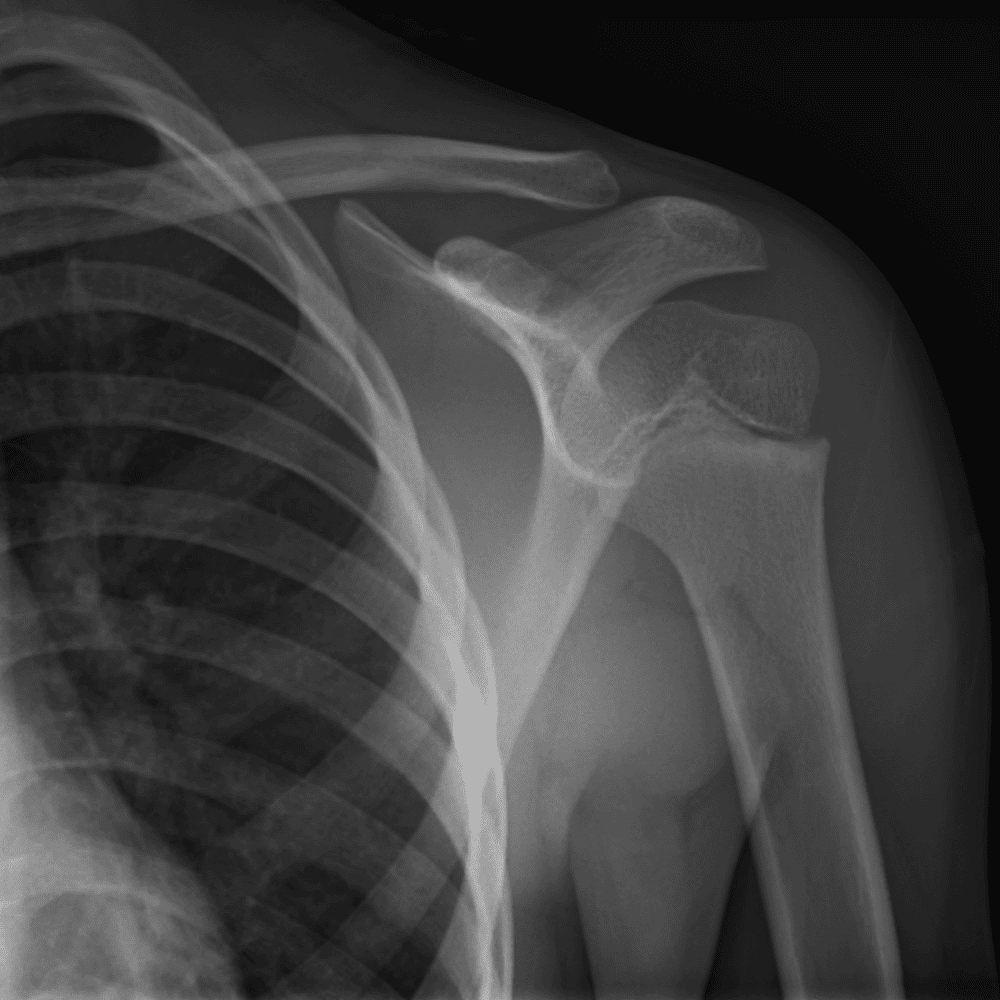

Simuliert den Dienst durch subtile oder schwierige Fälle und einige Normalbefunde.

30 Fälle